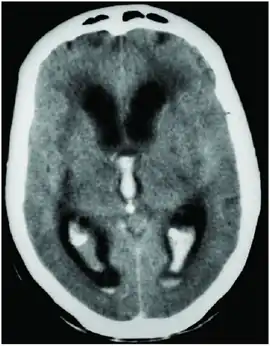

CT scan showing spontaneous intracerebral hemorrhage with bleeding in the third and both lateral ventricles and hydrocephalus[1]